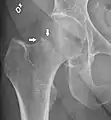

A case demonstrating a possible order of imaging in initially subtle findings:

X-ray showing a suspected compressive subcapital fracture as a radiodense line

CT scan shows the same, atypical for a fracture since the cortex is coherent

T1-weighted, turbo spin echo, MRI confirms a fracture, as the surrounding bone marrow has low signal from edema.